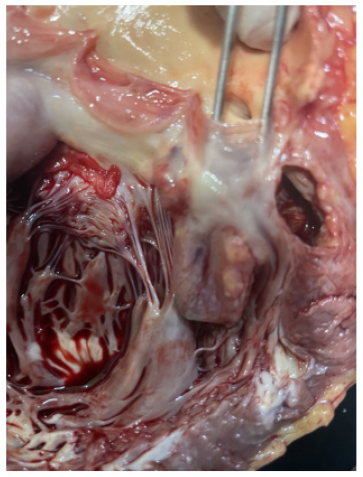

Figure 8 is post-mortem examination of cut section of left ventricle at aortic valve. It showed both right and left coronary ostia just above 3 cusps of aortic valve were normal; they were not occluded with clots.

Figure 9a-9b are post-mortem examination of cut section of left ventricle. The forceps pointed the aneurysm of Sinus of Valsalva; it was attached to posterior cusp of aortic valve. And it was close to left coronary ostia. The myocardium of the whole left ventricular was hyperemic indicating very extensive myocardial infarction.

Figure 8: Post-mortem examination of cut section showing intact both right and left coronary ostia just above 3 cusps of aortic valve.

Figure 9a: Post-mortem exasmination of cut section of left ventricle and the forceps pointing the aneurysm of Sinus of Valsalva attached to posterior cusp of aortic valve. The myocardium of left ventricular is hyperemic.

Figure 9b: Post-mortem examination of cut section of left ventricle and the forceps pointing the aneurysm of Sinus of Valsalva attached to posterior cusp of aortic valve. The myocardium of left ventricular is hyperemic.